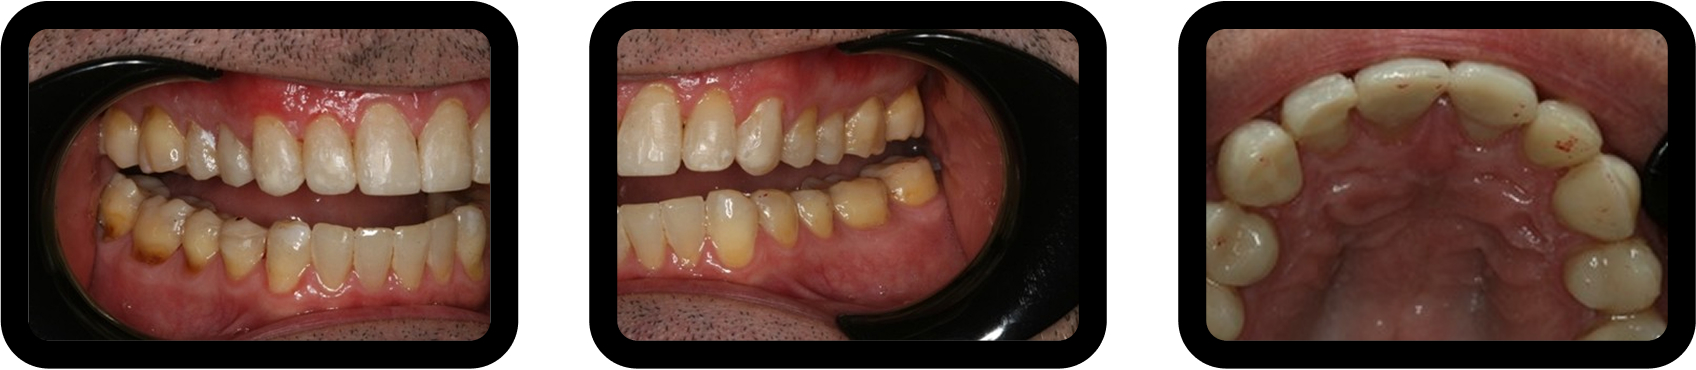

Digital scans were used to create a diagnostic wax-up and design posterior resin onlays (Fig. 9). Teeth were air-abraded to enhance adhesion, and onlays were bonded without tooth preparation.

Occlusion was equilibrated, followed by direct composite restoration of the anterior teeth, with emphasis on lingual contours to support the increased VDO (Fig. 10).

This conservative, staged approach protected dentition while preserving financial feasibility.

Phased restorative dentistry provided functional stabilization without immediate full-mouth reconstruction.